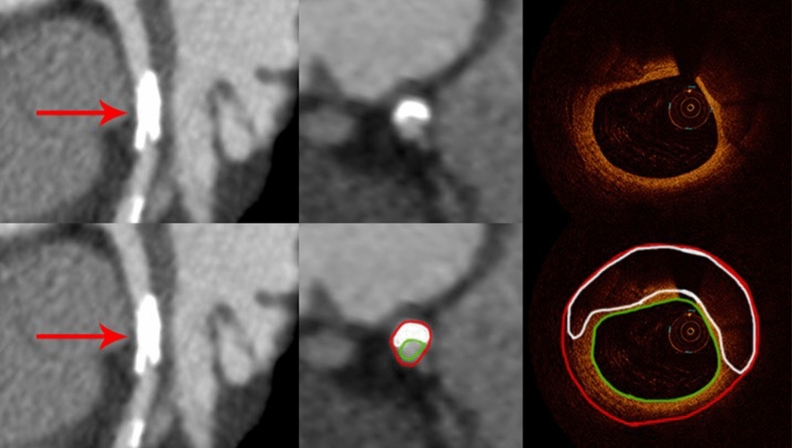

Among 87 calcified plaques visualized by OCT, 74 (85%) were identified by CCTA (Fig. 2) and 12 were not identified due to small plaque size (≤ 0.25 mm2) (Fig. 3). The sensitivity, specificity, positive and negative predictive values, and accuracy for detecting calcified plaque by CCTA were 87%, 100%, 100%, 87% and 89% respectively.

Figure 2.

Curved multiplanar reformation computed tomographic images (left) and cross-sectional (middle) views of the left anterior descending artery from CCTA (red arrows) show a densely calcified plaque with hyperattenuated signal. The corresponding OCT image (right) demonstrates a thick calcification with a distribution similar to that on CT. The red contour encompasses the interpolated vessel wall and the green outline the vessel lumen.